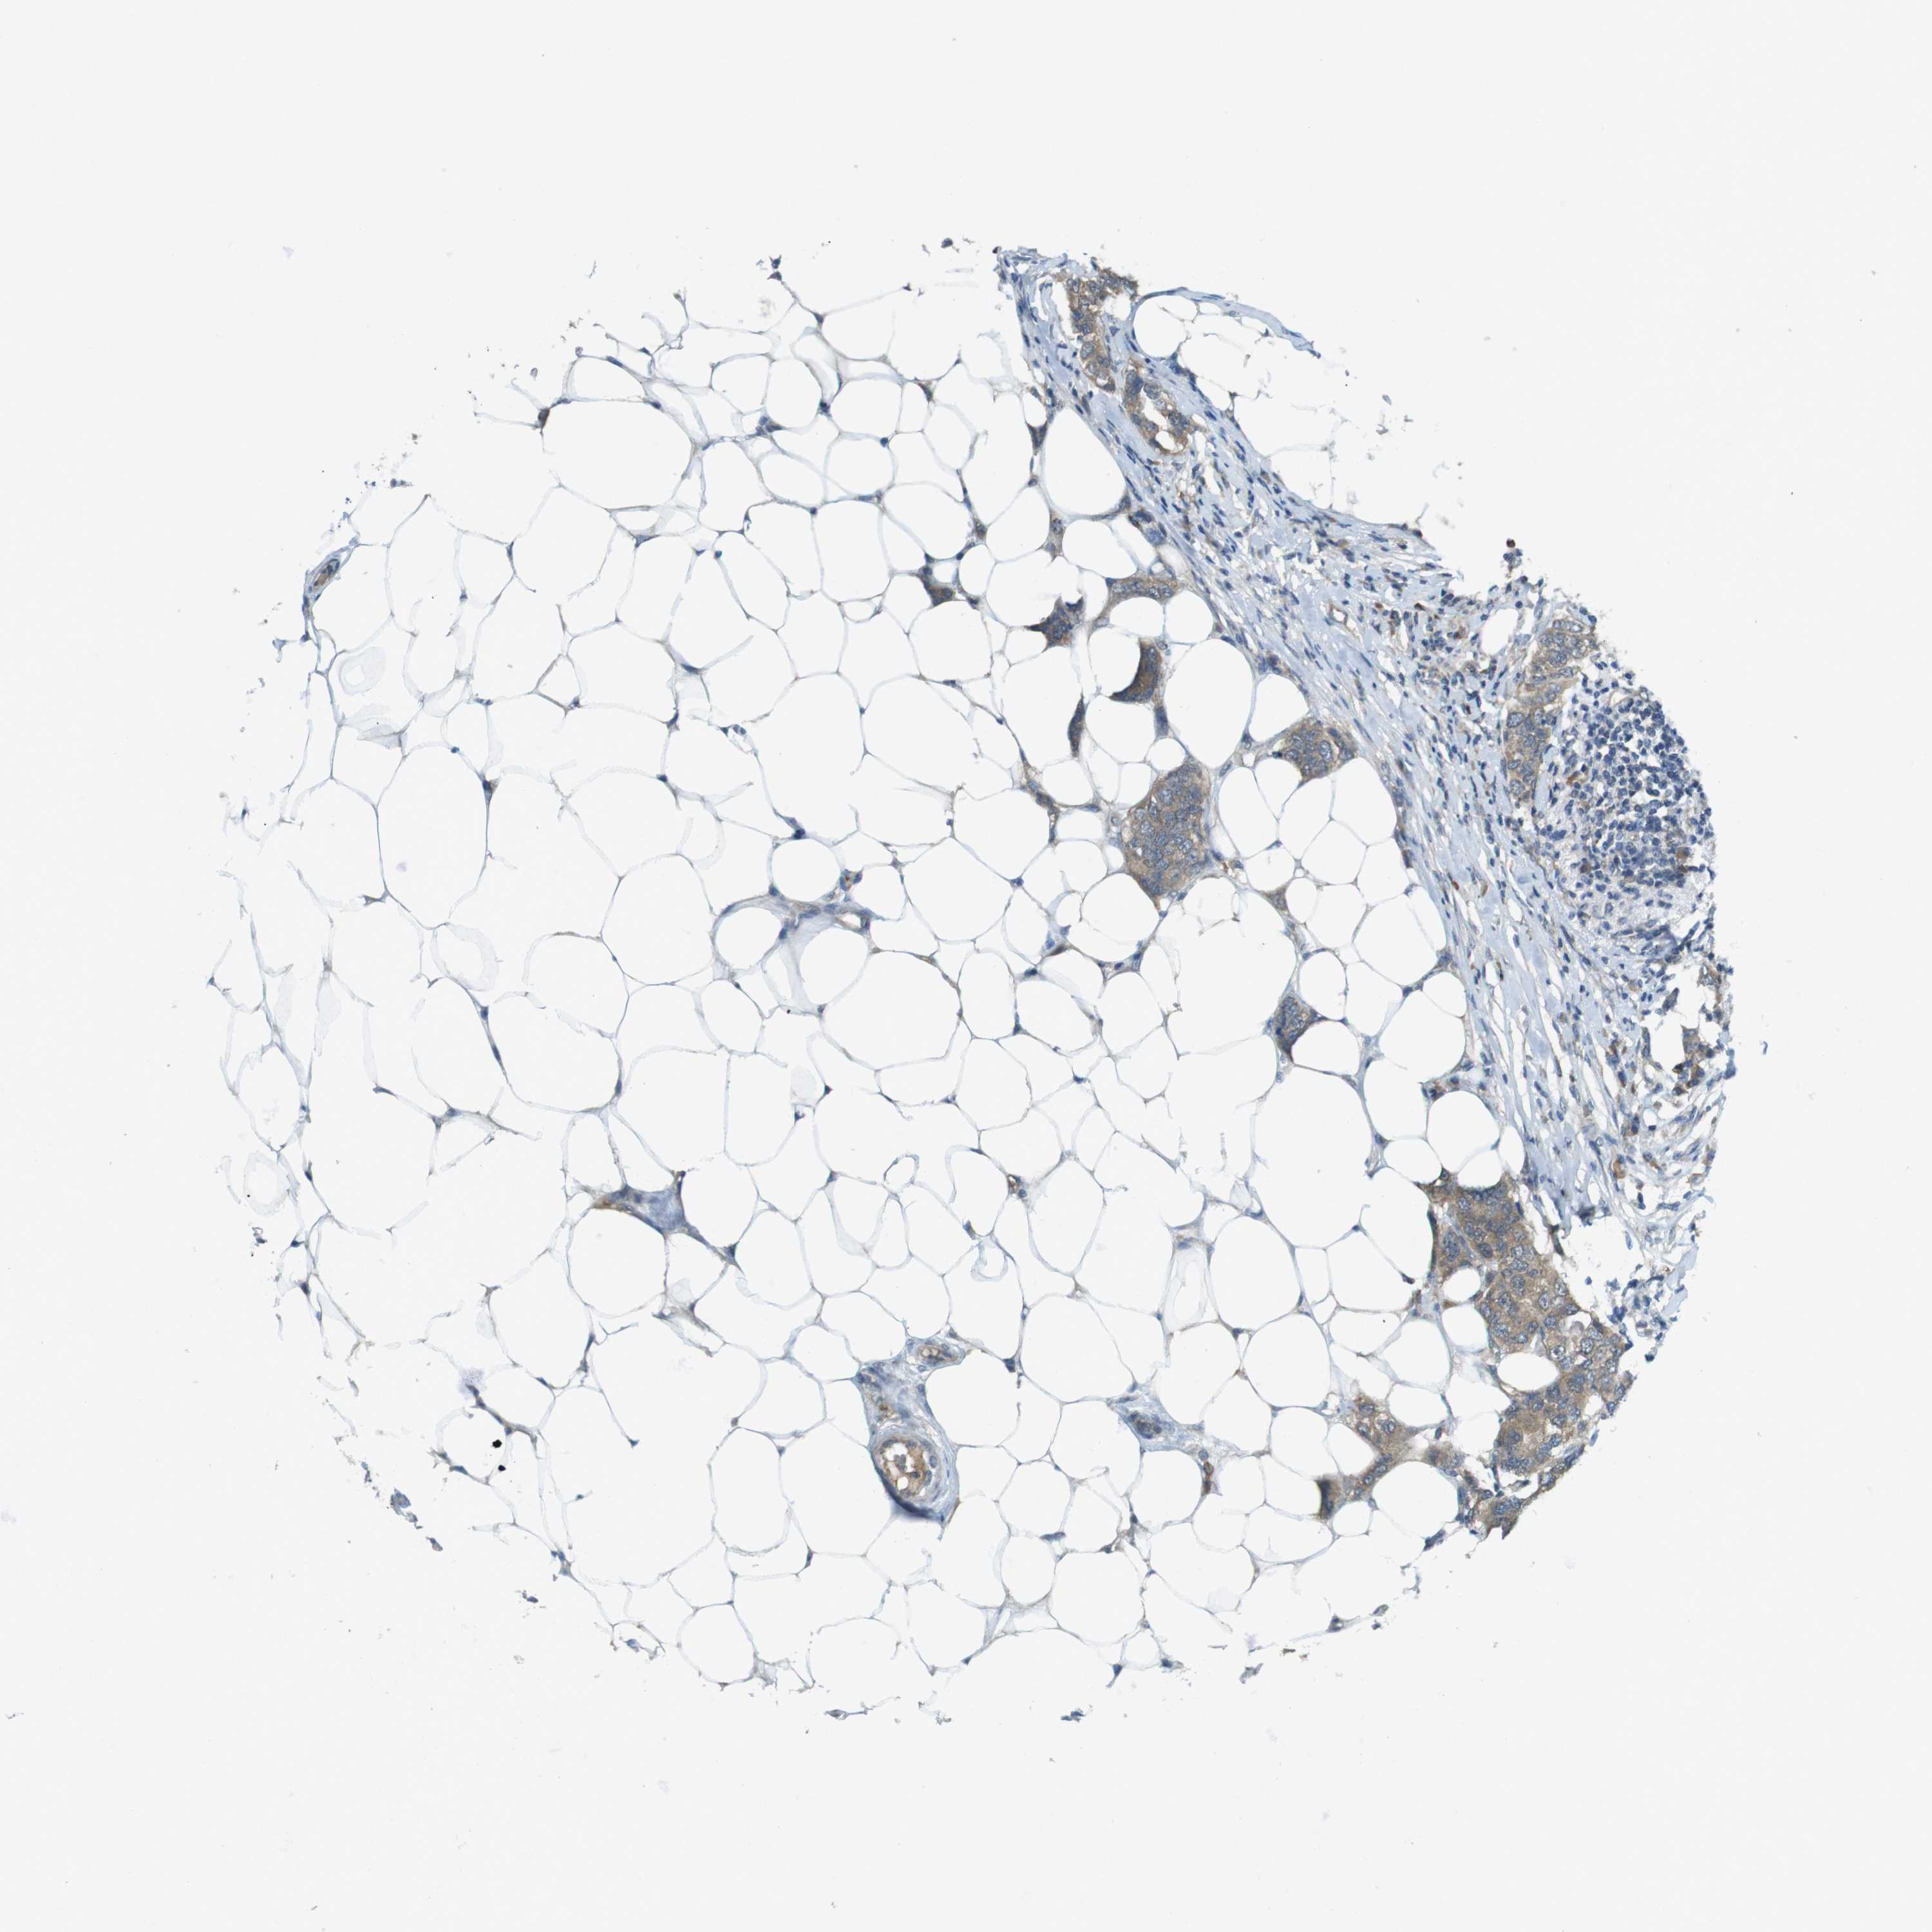

CANCER BREAST CANCER Show tissue menu

BRCA TCGA BRCA VALIDATION PROTEIN EXPRESSION